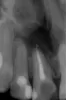

Необходимо удалить кисту 2-х передних зубов. В Крыму пока не нашли клинику, в которой возьмутся за это без удаления зубов. Т.е. сначала удаление, потом чистка с открытием полости через десну, далее полгода на временном протезе и после импланты.

Скажите, возможно ли выполнить все необходимые действия без удаления? Все-таки передние зубы для девушки много значат. Снимки прилагаю.

К сожалению, лечить тут уже нечего. Удаляйте зубы и не тяните, грануляция проникает в носовую перегородку.